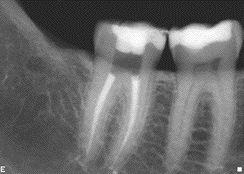

An Excellent Glide Path, the Road to Smoother Endodontics

FIGURE 5--Final shape after glide path refinement with .02 15 and 20 K3's in this vital lower molar.

Excellence in cleaning and shaping in endodontics stems from adherence to sound principles, including: 1) pre-operative assessment of the tooth for canal numbers, location, length and curvatures at all levels calcification, anomalous anatomy, access difficulties, etc.; 2) adequate visualization, ideally with a surgical microscope; 3) creation of straight line access to canals; 4) crown down … Read more